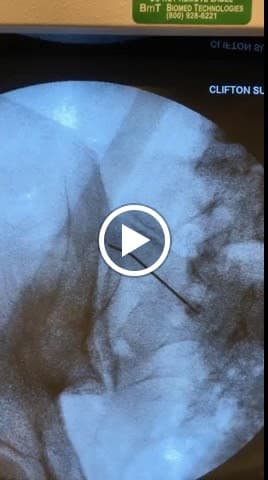

Nerve Blocks

Targeted nerve blocks to interrupt pain signals

Spinal Cord Stimulation

Implantable devices to manage chronic pain

Injection Therapy

Corticosteroid and other therapeutic injections for pain relief

Dr Koppel is Board Certified and Fellowship trained Regenerative and Interventional Pain Management with 20+ years of experience. Specializing in minimally invasive therapies for all conditions affecting the neck and back and joints. These can include herniated disks, spinal stenosis, and vertebrogenic conditions. Also specialized in regenerative therapies for treatments of all types of painful joint and spine conditions. These therapies include Platelet Rich Plasma, Stem Cell Therapy, Exosomes and Prolotherapy, among others Fellowship trained at The New York Hospital/Hospital for Special Surgery and Sloan Kettering Memorial Hospital